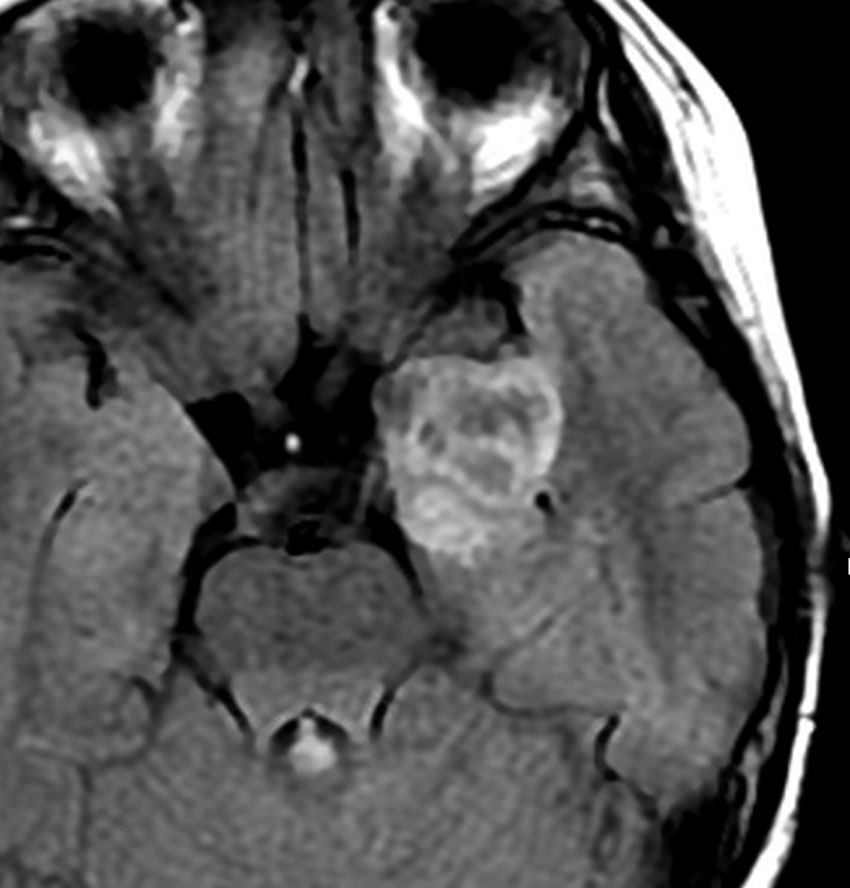

若い成人です,認知機能障害で発症しました。この画像を見るからに悪性神経膠腫,少なくともグレード3のグリオーマであることは明白です。しかし,グレード4膠芽腫あるいはグレード3退形成性星細胞腫にしては腫瘍周辺浮腫が軽すぎます。ですから,グレード3の退形成性乏突起膠腫 AO かも。認知機能の回復と温存を考量して,脳梁損傷と前交連損傷を避けて,右上前頭回と帯状回腫瘍を摘出しました。

左は術後のT1強調ガドリニウム増強像で,残存腫瘍がわかります。この腫瘍に対してICE (IFO/CDDP/VP-16) 化学療法を1コースしました。右側のMRIが1ヶ月後の画像です。このように1p/19q欠失のある退形成性乏突起膠腫は,化学療法感受性がとても高い悪性グリオーマです。ですから,手術で後遺症を残さないように,勢い込んで腫瘍を摘出しようとしないことが大切です。光顕診断はAOで,後々の解析で1p/19q codeletion でした。